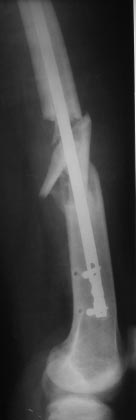

Уважаемые коллеги, наконец пациент явился на повторный осмотр, через два

с половиной месяца после операции.

Был рекомендован постельный режим в течение одного месяца, после

контрольная Р-графия и потом решить, но со слов б-ного постельный режим

10 дней, ходьба при помощи костылей и палочки еще дней 20, и уже более

полутора месяцев ходит без палочек, самостоятельно, с полной нагрузкой.

При осмотре ось бедра правильная, активно поднимает ногу, укорочения

нет, пальпаторно безболезненный, амплитуда движений в коленном суставе

около 80гр.: 80/0/5. (якобы коленный сустав не разрабатывал из-за боязни

боли).

Рекомендована активная разработка движений.

Выложил Р-снимки и фото.

С уважением Абдурашид.